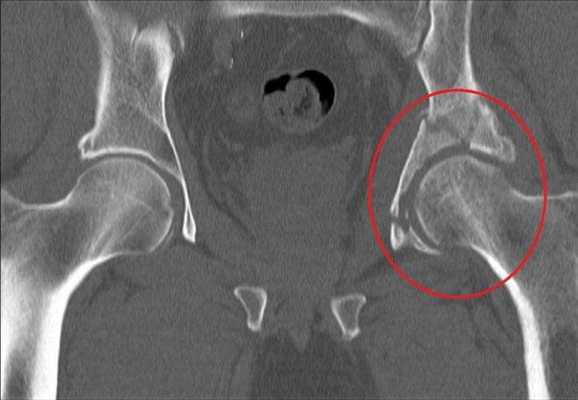

Переломы вертлужной впадины обычно возникают вследствие ДТП или падений с высоты. Кости таза при этом ломаются и нередко смещаются.

Перелом правой вертлужной впадины(на снимке слева).

Деструкция вертлужной впадины

По статистике, переломы тазовых костей случаются у людей в возрасте 21-40 лет. Их основные причины - автомобильные аварии и серьезные бытовые травмы. Переломы вертлужной впадины составляют около 15-20% всех травматических повреждений таза. Они сопровождаются переломами и вывихами головки бедренной кости.

Неосложненные переломы вертлужной впадины у людей молодого возраста лечат без хирургического вмешательства. Операция требуется при Т-образных переломах, интерпозиции обломков в суставе, невправившихся переломовывихах и массивных переломах заднего края впадины.